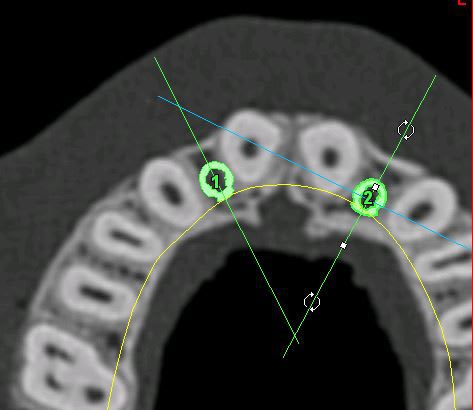

je mets les coupes et les radios post op...

intervention "quasi" flaless, juste des incisions crestales en W pour manager les papilles...

Plc12 hhx60b - Eugenol

Pl12 u0n8gy - Eugenol

Plc22 trdesx - Eugenol

Pl22 on1tll - Eugenol

Pl1222 zuoj0h - Eugenol

12 xdpxmw - Eugenol

22 w4rsbx - Eugenol

très honnêtement c'est bien mais je ne vois absolument pas pourquoi il faut guider l'instrument dans un cas comme ça, car pour la latéralité, tu suis les axes des autres dents, avec précautions ok mais bof, et pour l’épaisseur, c'est un boulevard

j'ai fais ça à main levée, et c'est tout simplement à la porté de tout praticien consciencieux, ce qui n'enlève rien au coté intéressant de ton outil.

c'est un boulevard en épaisseur, ok...

l'intérêt...c'est qu'en une petite heure c'était plié, provisoires inclues...et sans ouvrir grand pour contrôler les proximités radiculaires et faire radio sur radio de contrôle pour ne pas toucher aux racines...

"time is money", et sur cette intervention, au bas mot, c'est une bonne heure de gagnée vs intervention "classique"...